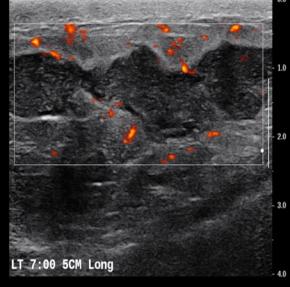

[Breast] 35 /F, Palpable mass, left with redness

Diagnosis Idiopathic granulomatous mastitis

Comments Idiopathic granulomatous mastitis (IGM) is a rare benign inflammatory breast entity characterized by lobulocentric granulomas. IGM has a persistent or recurrent disease course and affects parous premenopausal women with a history of lactation. It has also been associated with hyperprolactinemia. The most common clinical sign is a palpable tender mass. However, the nonspecific manifestations and varied demographic features of this condition, as well as the other similar-appearing and superimposed breast entities, pose substantial diagnostic challenges. Entities with similar manifestations include inflammatory breast cancer (IBC), infective mastitis, foreign body injection granulomas, mammary duct ectasia, diabetic fibrous mastopathy, and systemic granulomatous processes. The strategy for imaging IGM depends on patient age, clinical manifestations, and risk factors. Targeted ultrasonography, mammography, and less commonly, magnetic resonance imaging have proven to be useful for imaging evaluation. Core-needle biopsy, with or without fine-needle aspiration for cytopathologic examination, and culture analysis are usually required to exclude IBC and other benign inflammatory breast processes. Patients with IGM have an excellent prognosis when they are appropriately treated with oral steroids or second-line immunosuppressive and prolactin-lowering medications. However, surgical excision may be an option for patients in whom medication therapy is unsuccessful. Imaging surveillance can be offered to patients with incidentally encountered IGM or mild symptoms. Clinical suspicion for this rare disease and the breast imager’s prompt diagnosis can lead to an improved patient outcome. The purpose of this article is to review the imaging manifestations of IGM in a multimodality case-based format and to describe relevant clinical and imaging-based differential diagnoses. The associated pitfalls, epidemiologic and histopathologic factors, clinical manifestations, natural course, and management of IGM also are discussed.